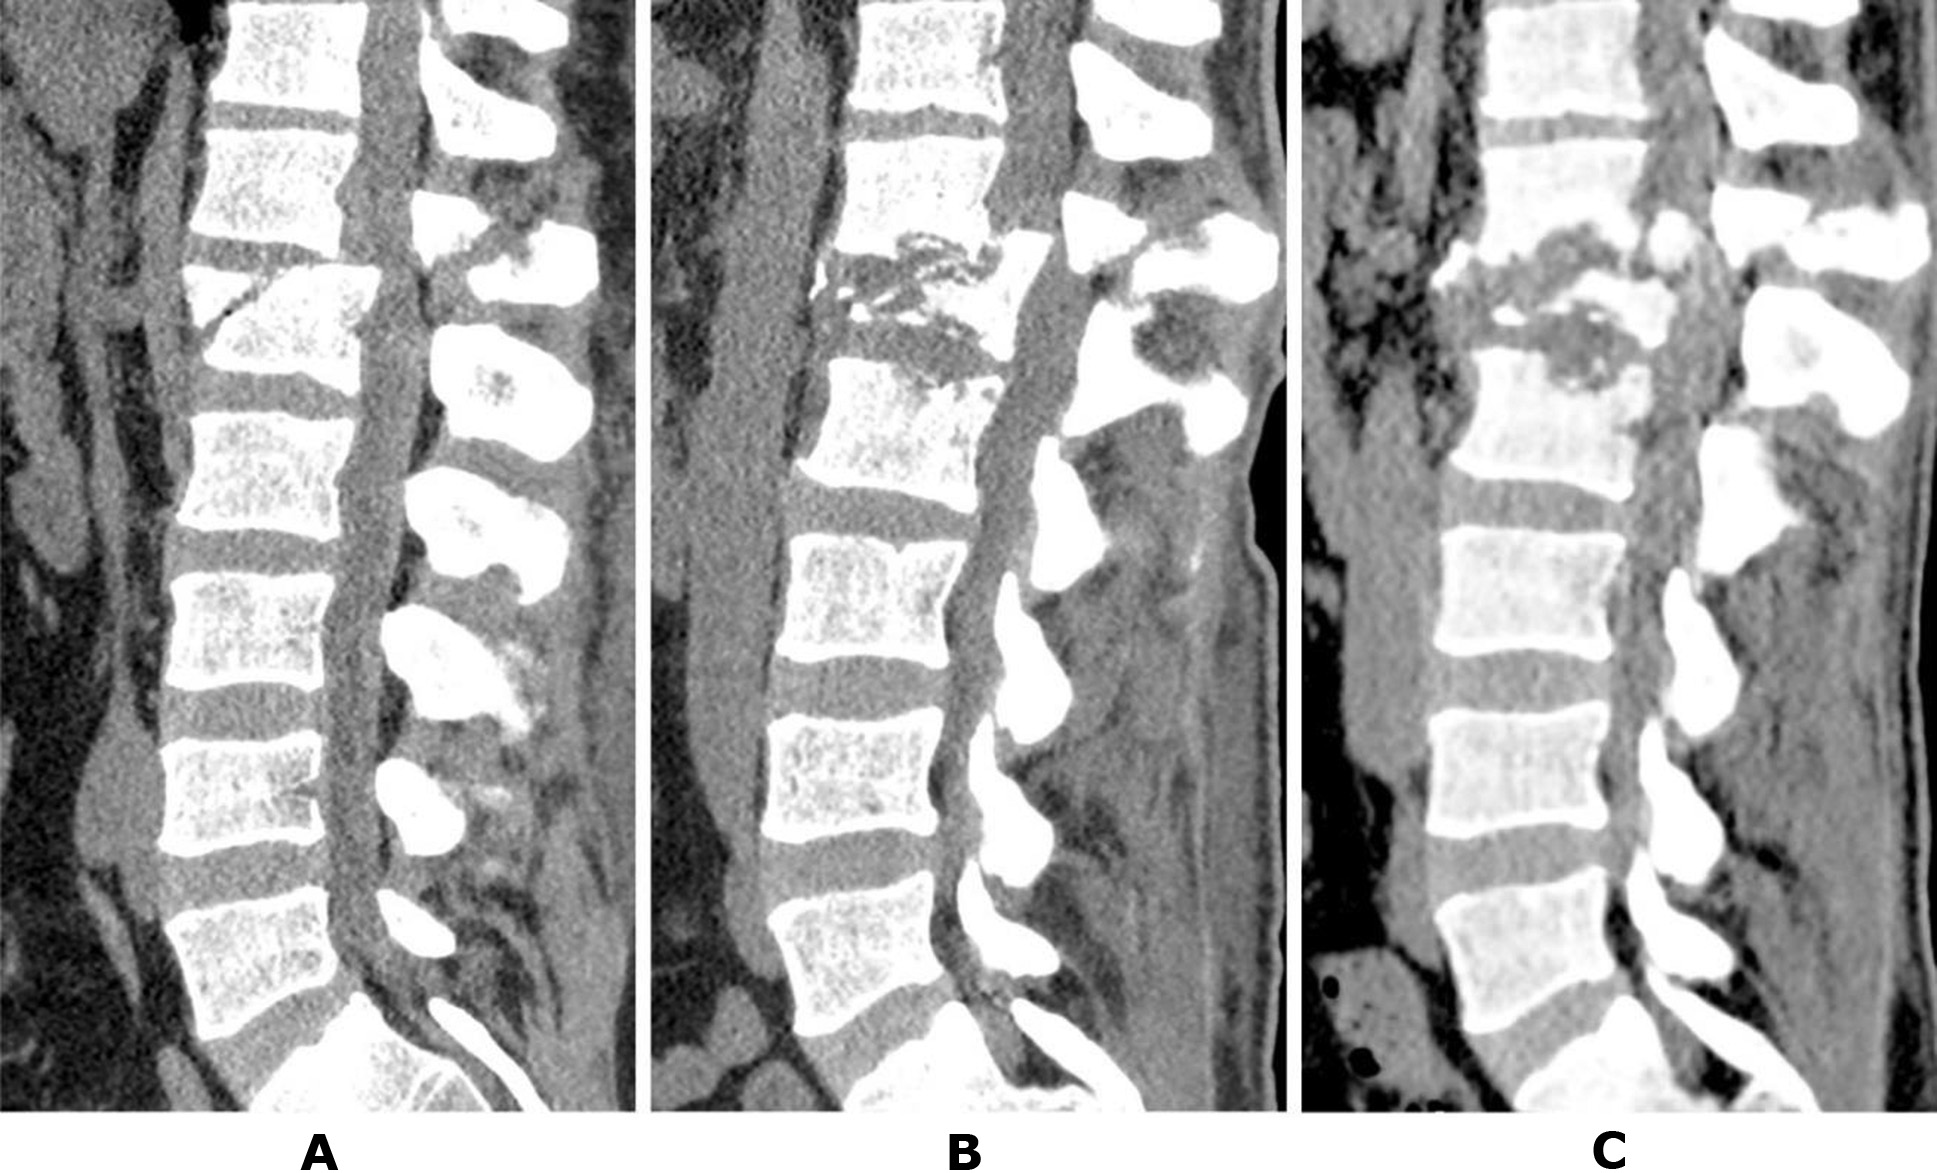

On the second day post-injury, CT scans of the cervical, thoracic, and lumbar spine were conducted. Diagnosed injuries included a compression fracture of the L1 vertebral body, fractures of the superior facet joints of L1, and the inferior facet joints of Th12, with the fracture line extending to the spinous process of Th12. Significant compression of spinal canal structures was identified due to anterolisthesis of the Th12 vertebral body, with an 11 mm forward displacement, corresponding to type C injuries (Fig. 2A).

At the request of the patient's relatives, he was transferred to the Romodanov Institute of Neurosurgery, NAMS of Ukraine, for surgical intervention. During preparation for the transfer, a follow-up CT scan of the thoracolumbar spine was performed at the hospital, revealing significant lysis of the anterior two-thirds of the L1 vertebral body (Fig. 2B). Upon admission to the Romodanov Institute of Neurosurgery (2 months post-injury), a CT scan revealed almost complete lysis of the L1 vertebral body: the anterior sections were not visualized, and the posterior sections consisted of isolated bone fragments. Additionally, the process extended to the endplates of the adjacent vertebrae, Th11 and L2. At the time of admission, the leukocyte count was 8.8 × 10⁹/L, and the C-reactive protein (CRP) level was 3.1 mg/L. Bacteriological analysis of intraoperatively obtained samples (three specimens from the lysis zone of the L1 vertebral body) showed no microbial growth.

Fig. 2. Patient T., 41 years old. CT scans of the lumbar spine: A – the day after the injury; B – after 1.5 months; C – after 2 months post-injury (details in the text)